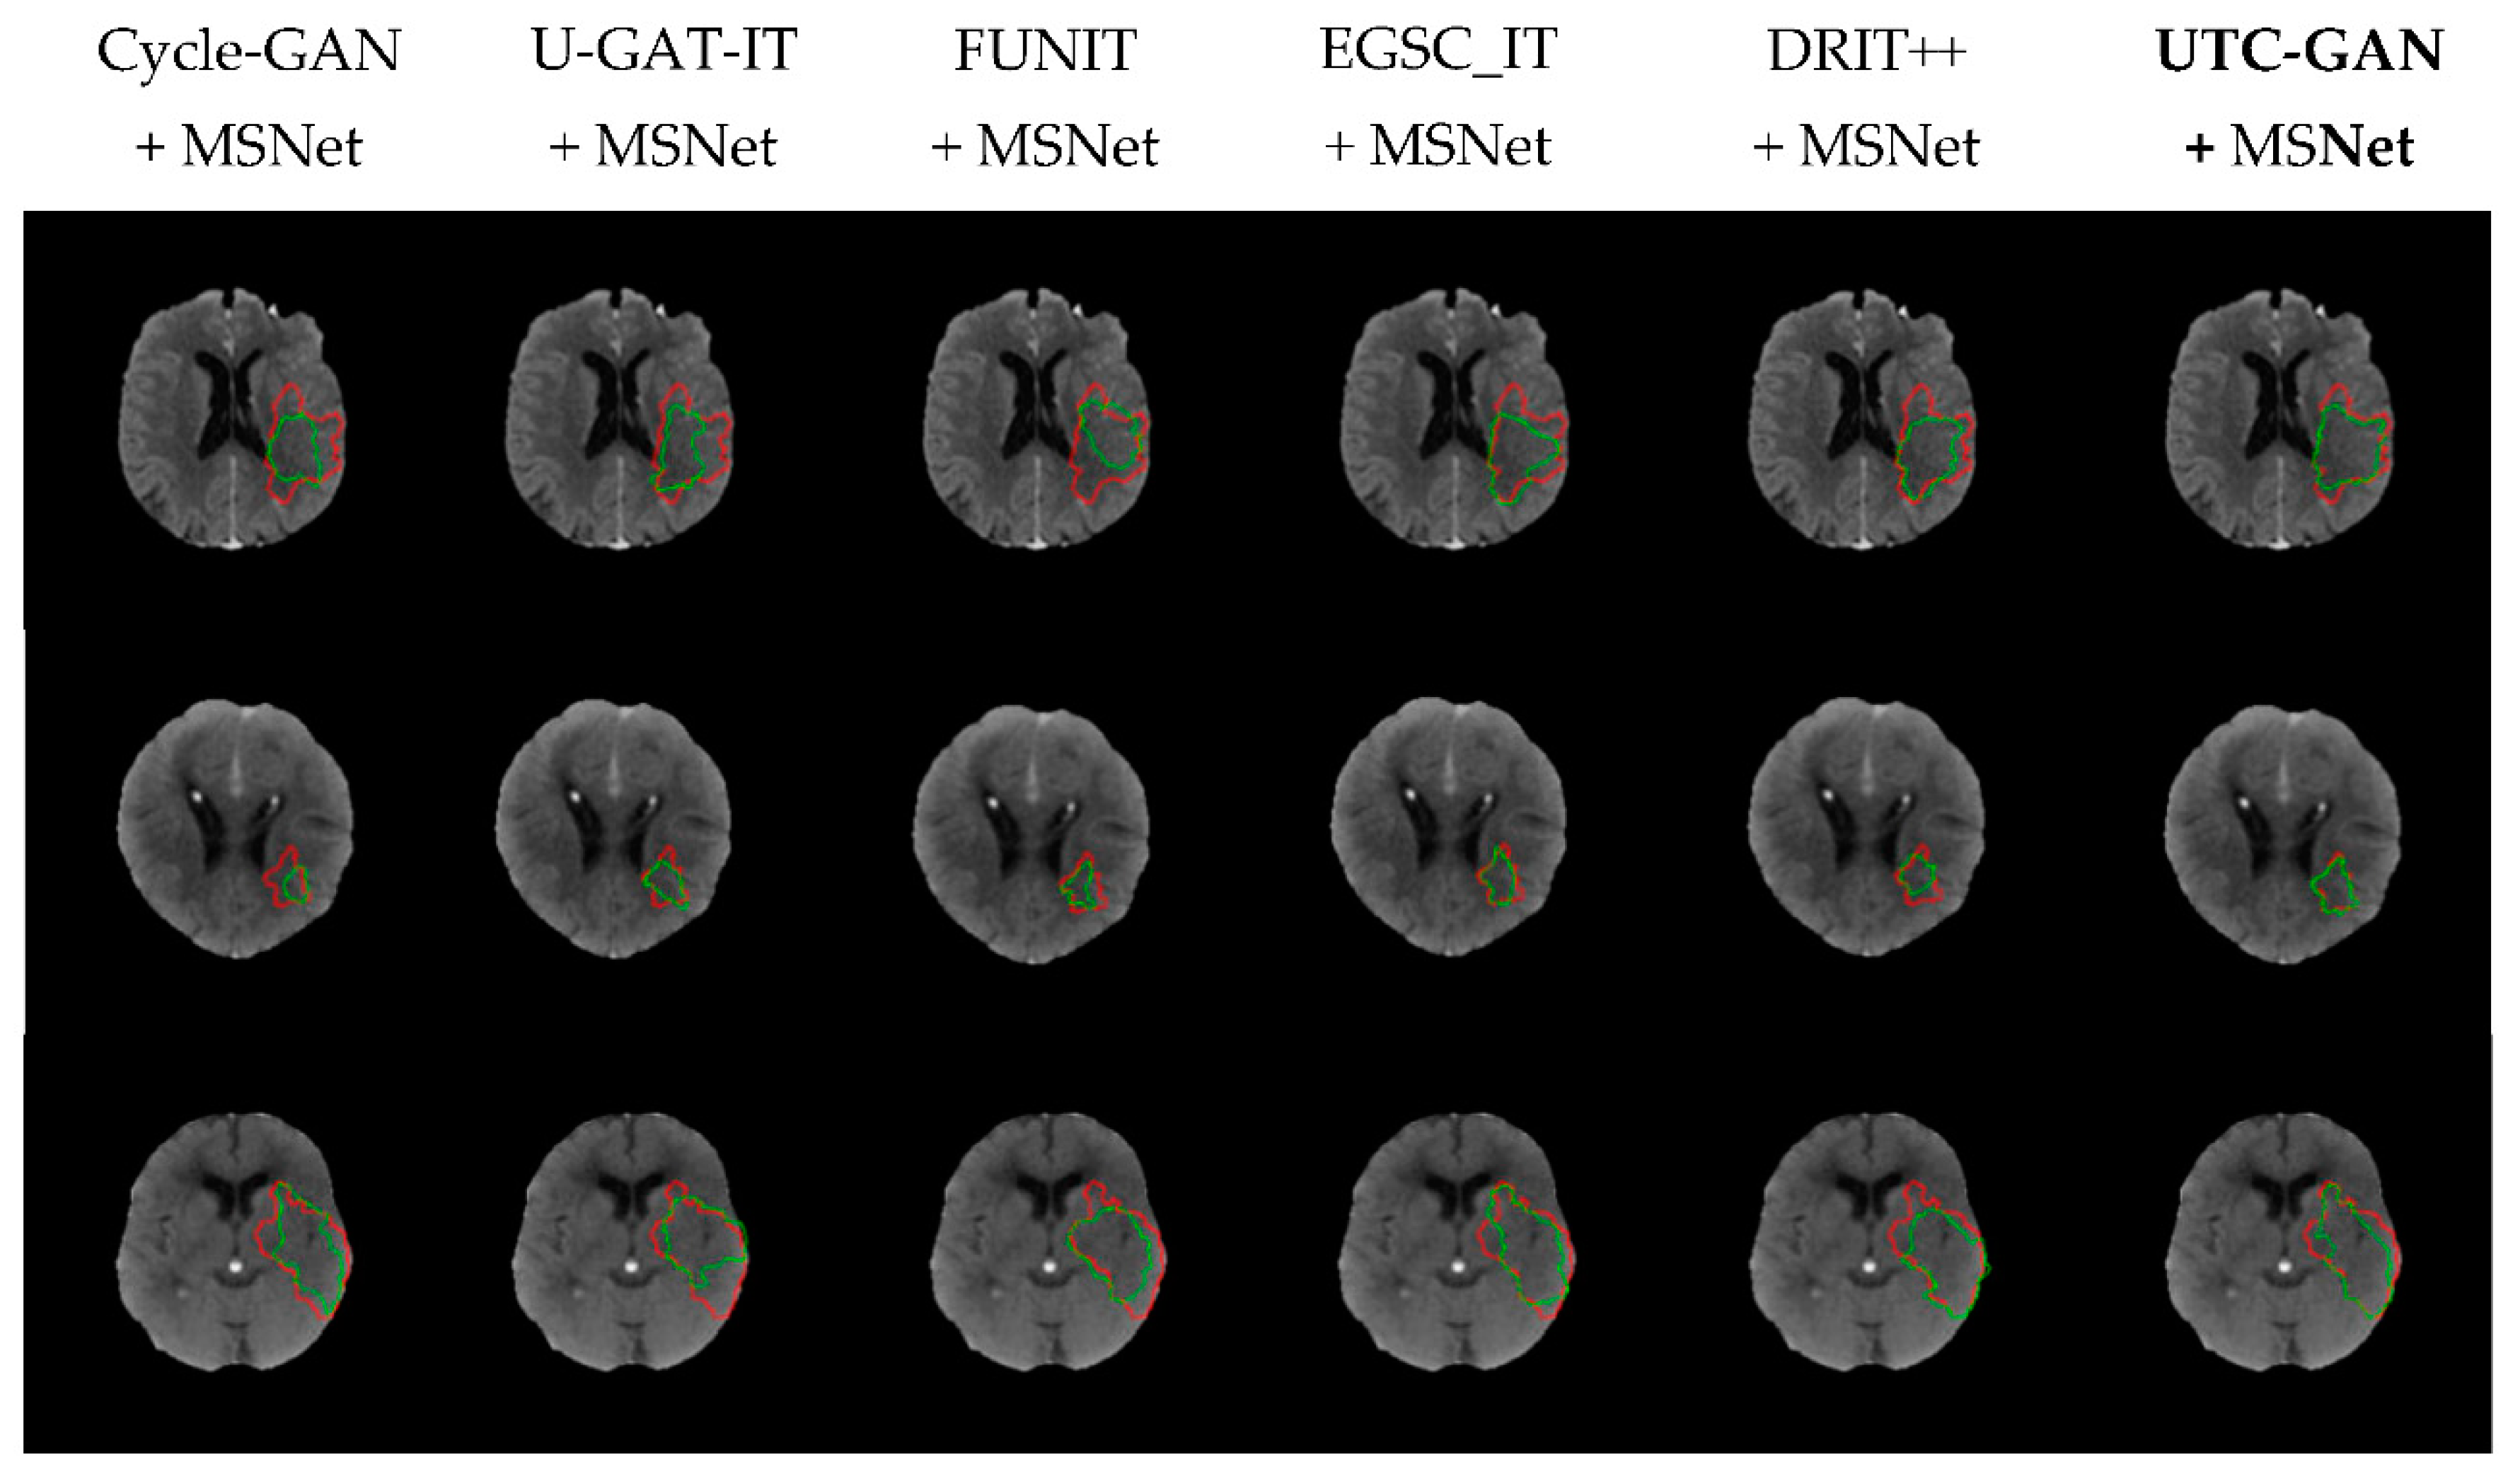

| Method | Dice Coefficient | IoU | Precision | Accuracy | Recall | Hausdorff Distance (mm) |

|---|---|---|---|---|---|---|

| MSNet | 0.675 | 0.578 | 0.721 | 0.894 | 0.699 | 27.03 |

| Cycle-GAN + MSNet | 0.709 | 0.633 | 0.773 | 0.903 | 0.725 | 25.00 |

| U-GAT-IT + MSNet | 0.684 | 0.602 | 0.745 | 0.907 | 0.687 | 24.21 |

| FUNIT + MSNet | 0.718 | 0.645 | 0.786 | 0.912 | 0.732 | 20.34 |

| EGSC-IT + MSNet | 0.751 | 0.683 | 0.809 | 0.925 | 0.773 | 34.11 |

| DRIT++ + MSNet | 0.735 | 0.669 | 0.781 | 0.915 | 0.758 | 19.99 |

| UTC-GAN + MSNet | 0.768 | 0.685 | 0.820 | 0.926 | 0.781 | 17.73 |